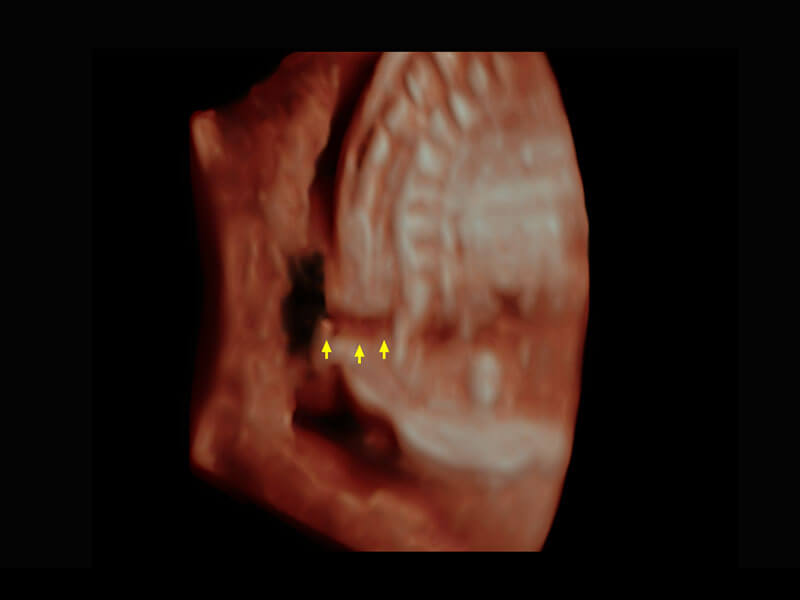

腔內(nèi)三維-宮內(nèi)節(jié)育器

腔內(nèi)三維-光影成像